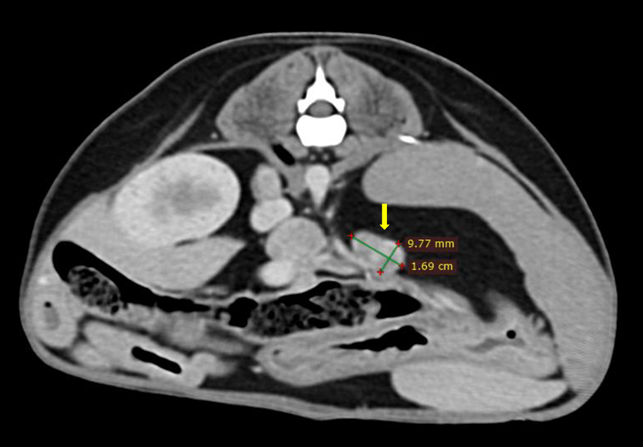

(๊ทธ๋ฆผ2. ๋น์ฅ ๋ฐ ๊ฐ ๋ฆผํ์ ์ข

๋)